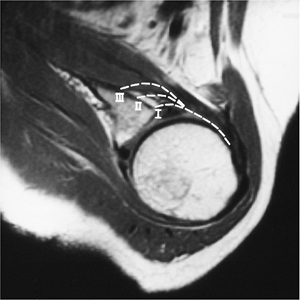

![]() |

FIGURE 7-26 Axial MR image demonstrating the types of capsular attachment (broken lines): Type I at glenoid margin, Type II just medial to margin, and Type III more than 1 cm beyond the glenoid margin.